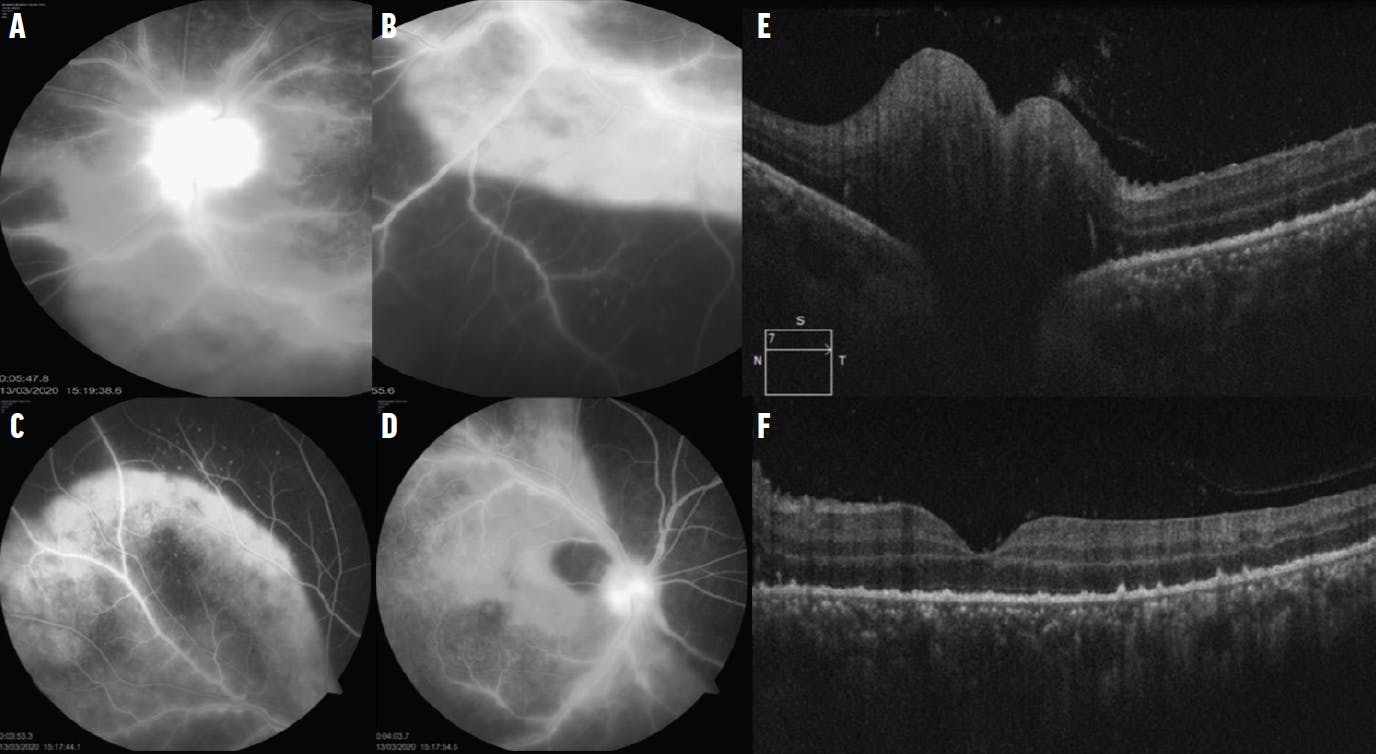

Figure 2. FA of the left eye (A) showed disc leakage with well-defined staining of choroidal lesions (B, C) and vascular staining in the right eye (D). OCT of the left eye showed disc edema (E) and hyper-reflective dots at the subretinal and choroidal level (F).

A 41-year-old patient presented to our clinic with painless loss of vision in each eye for the last 2 weeks. BCVA was 6/60 OD and counting fingers OS. The anterior segment examination was normal. Fundus examination of the right eye showed disc hyperemia with marked yellowish-white choroidal plaque-like lesions over the posterior pole with retinal periphlebitis and vitreous bead-like opacities (Figure 1, A). The left eye showed marked disc edema with choroidal lesions along the arcade blood vessels and peripheral vessel sheathing (Figure 1, B). Fluorescein angiography (FA) and OCT confirmed the active chorioretinitis lesions along with disc leakage (Figure 2).